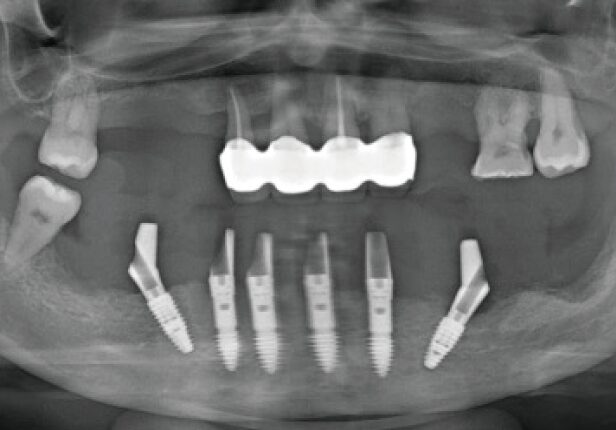

Mandibular Full case

Pre-surgery panorama

Post-surgery panorama